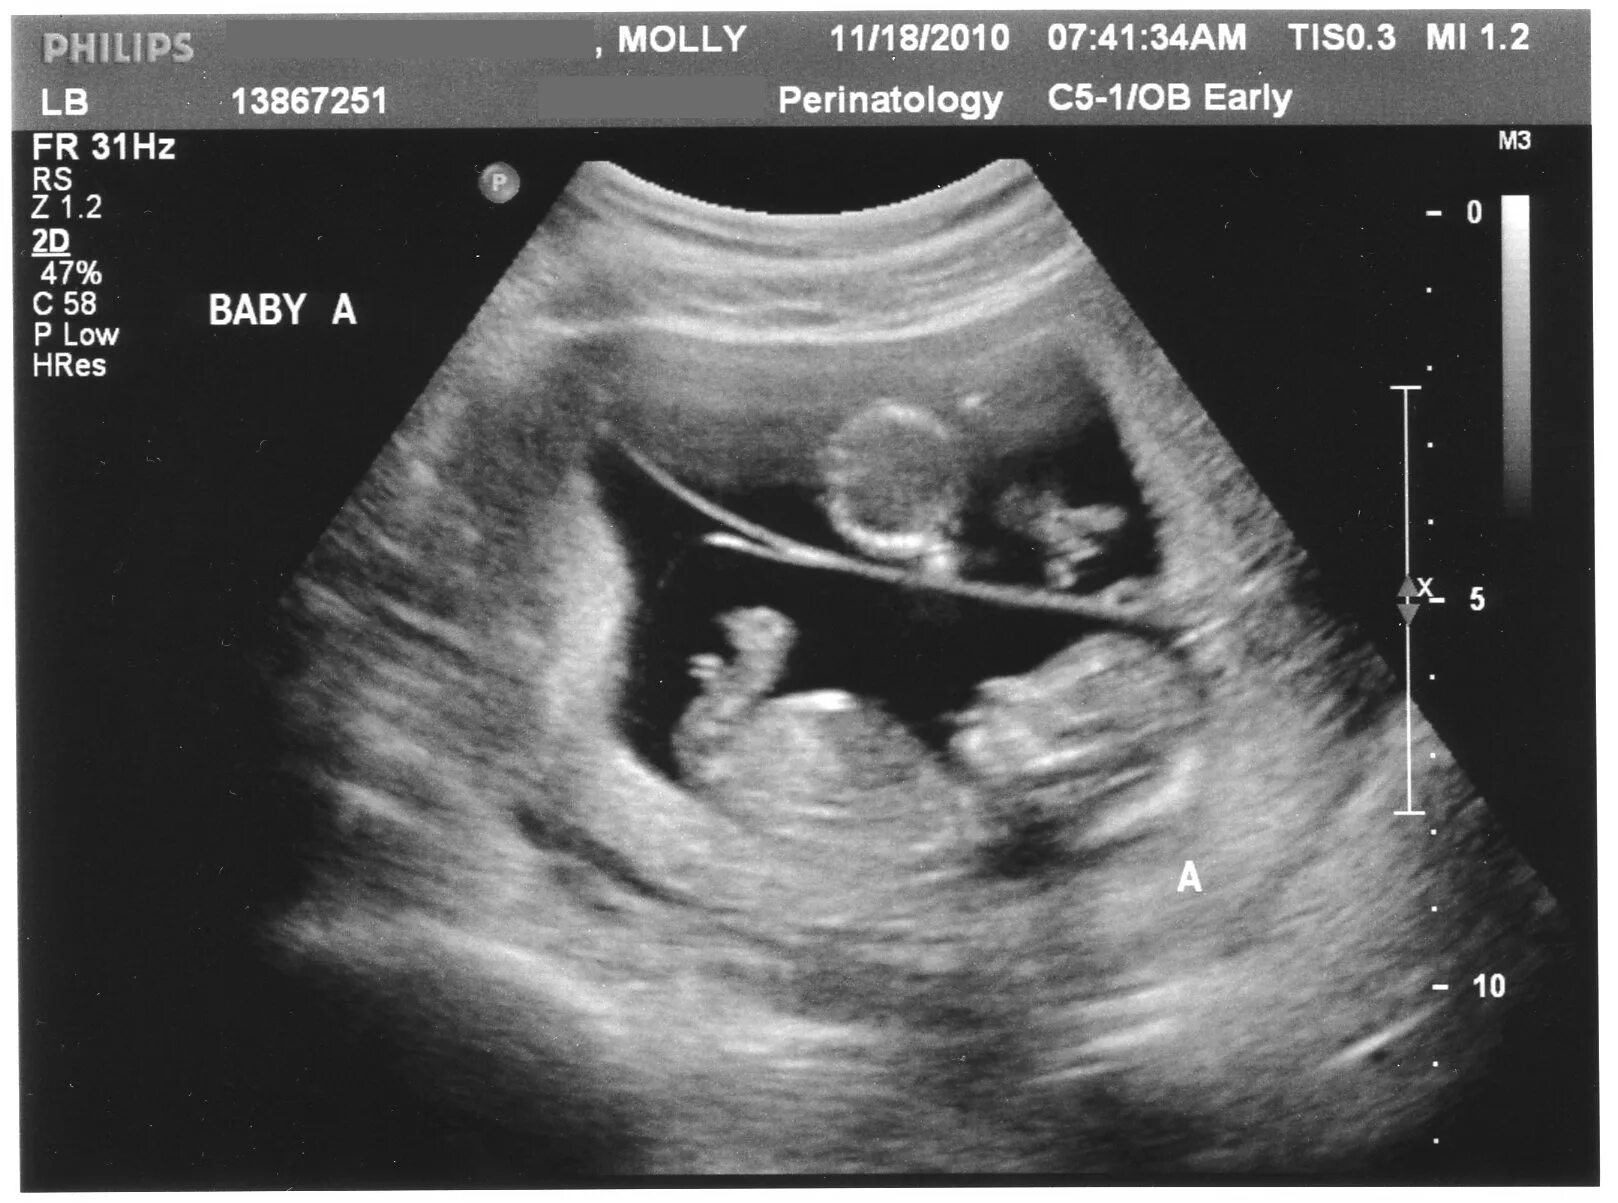

26 неделя 2025